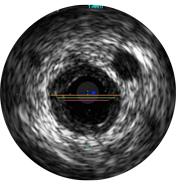

Intravascular ultrasound (IVUS) is a catheter-based imaging technology that allows physicians to visualize blood vessels from the inside out. Cross-sectional images help assess presence and extent of disease, plaque geometry and morphology, guide wire position during lesion crossing, and stent position post-treatment. The imaging transducer emits high-frequency sound waves that echo off vessel walls and are sent back to the system in varying intensities depending on the tissue. System electronics process the signal to display the cross-sectional image.

Vessel diameters may be determined at proximal and distal reference sites by obtaining lumen diameters, mid-wall diameters (halfway between lumen and vessel), or vessel diameters, in order of increasing aggressiveness.

If maximum and minimum diameters are used, measurements should bisect the geometric center of the vessel rather than the center of the IVUS catheter.